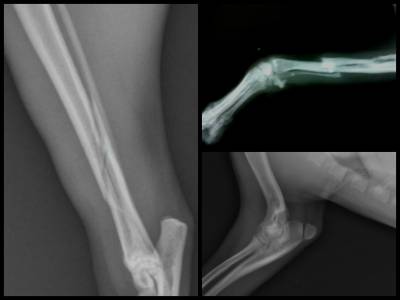

В першу чергу лікар усуне біль і занепокоєння (седативні препарати), обробить рану (якщо зовнішні пошкоджені тканини). Так як визначити у собаки перелом лише за зовнішніми ознаками не завжди можливо, обов’язково роблять знімок. Рентген допоможе оцінити ситуацію: іноді для зрощування досить гіпсу, а іноді потрібне хірургічне втручання – повернути краю зламаної кістки в природне положення, видалити дрібні осколки, відновити цілісність судин і м’язів.

Іноді потрібно стягнути/скріпити кістка шурупами, пластинами, спицями з металу – ювелірна робота, дорога, але результати вражають. В деяких випадках потрібна заміна ушкодженої ділянки кістки на протез. Наприклад, при переломі шийки стегна у собаки набагато більше шансів повністю відновитися, якщо відразу замінити суглоб. Особливо, коли мова йде про людей похилого віку, м’язистих або ожирілих собаках.